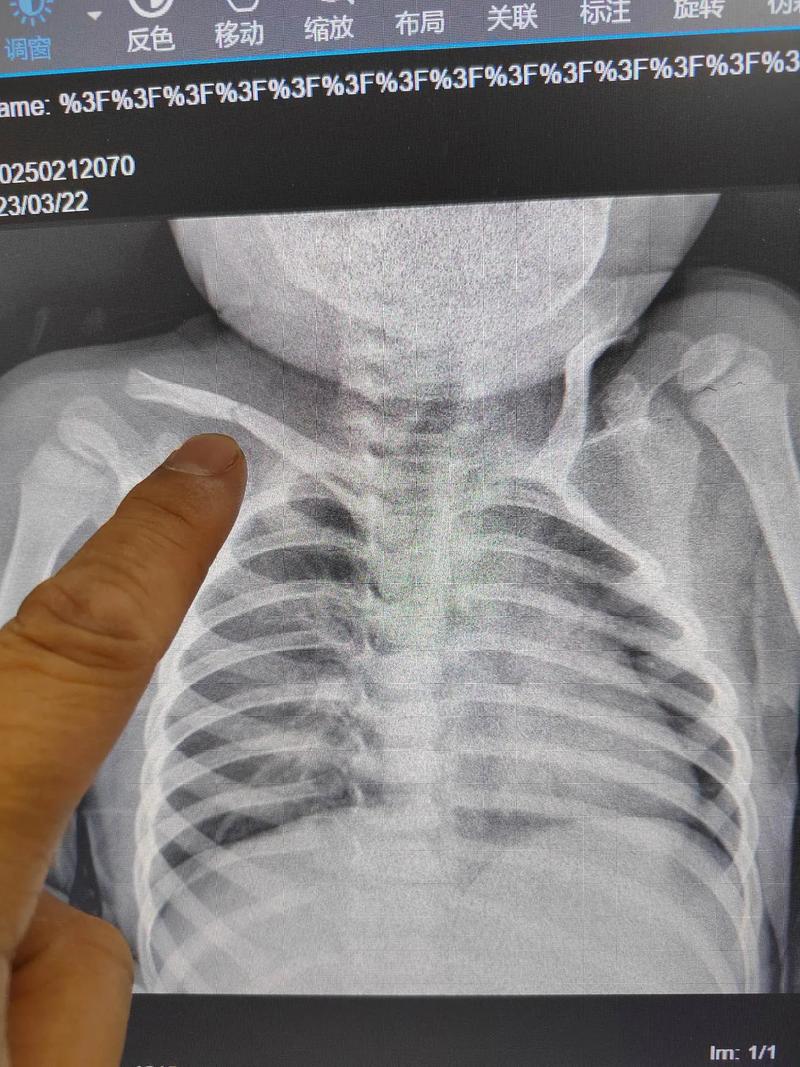

- 如果怀疑是骨折,医生可能会建议拍一张锁骨的X光片,这是确诊的金标准,X光片可以清楚地显示是否有骨折线、移位以及骨痂形成的情况。